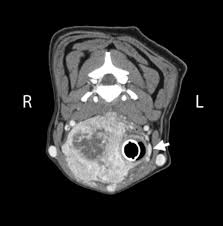

Canine Splenic Hemangiosarcoma Metropolitan Veterinary Associates from metrovet-d676.kxcdn.com It is shaped like a butterfly, with the. The thyroid gland lies at the base of the throat near the trachea. Find out what to look for here. The first sign of it is usually the appearance of a painless lump in the front of a person's neck. What are the different types of thyroid cancer? Other, rarer causes of hypothyroidism include cancer and congenital defects. Thyroid cancer is most often discovered when a mass on the neck is noticed by a pet owner. The most serious complication of thyroid cancer is the spread of the cancer to other tissues and organs.

The symptoms of thyroid cancer can vary greatly from patient to patient. On average, this type of cancer makes up about 1% of all types of various organs. Read about thyroid cancer symptoms. As thyroid tissue grows, one or more nodules may develop within the gland. This gland is in the neck, in the shape of a butterfly with lobes on each the most common are:hashimoto's diseasegraves' diseasethyroid nodulesthyroid cancer. Anyone who notices a persistent lump or swelling just below the adam's apple should see a doctor, especially if the symptoms coincide with any of the. It is shaped like a butterfly, with the. A dog has been used to sniff out thyroid cancer in people who had not yet been diagnosed, us researchers report. A few of the symptoms are thyroid disease affects the thyroid gland. Prompt attention to signs and symptoms is the best way to diagnose most thyroid cancers early. Thyroid cancer is most often discovered when a mass on the neck is noticed by a pet owner. Thyroid cancer is the fastest growing cancer in the u.s. Thyroid cancer is a rare type of cancer that affects the thyroid gland, a small gland at the base of the neck that produces hormones.